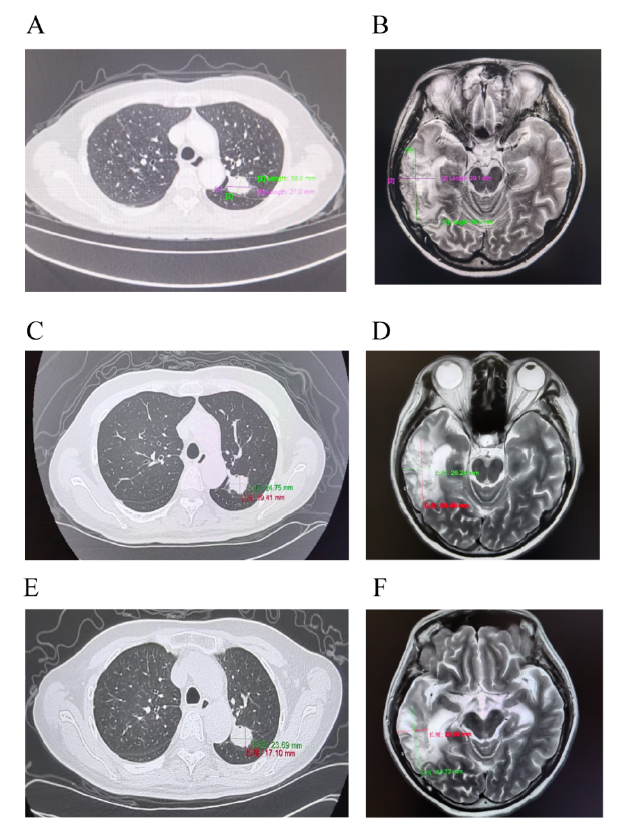

病灶持续缩小:2025年5月及7月两次影像学复查显示,疾病稳定(SD)且病灶持续缩小(颅内60mm→53.72mm;肺部27mm→23.69mm),见图2。截至2025年7月31日,全身及颅内PFS均超6个月。目前患者仍继续接受联合治疗,疾病控制良好。

图2. 患者接受佐利替尼+伏美替尼联合治疗的肺部和脑部病变的随访影像学检查

(A)联合治疗前胸部CT(B)联合治疗前脑部MRI(C)2025年4月30日胸部CT,3个月随访时肺部病变稳定(D)2025年4月29日脑部MRI,3个月随访时残留软脑膜增强(E)2025年6月30日胸部CT,5个月随访时病情持续稳定(F)2025年7月1日脑部MRI,5个月随访时脑沟增强进一步减轻